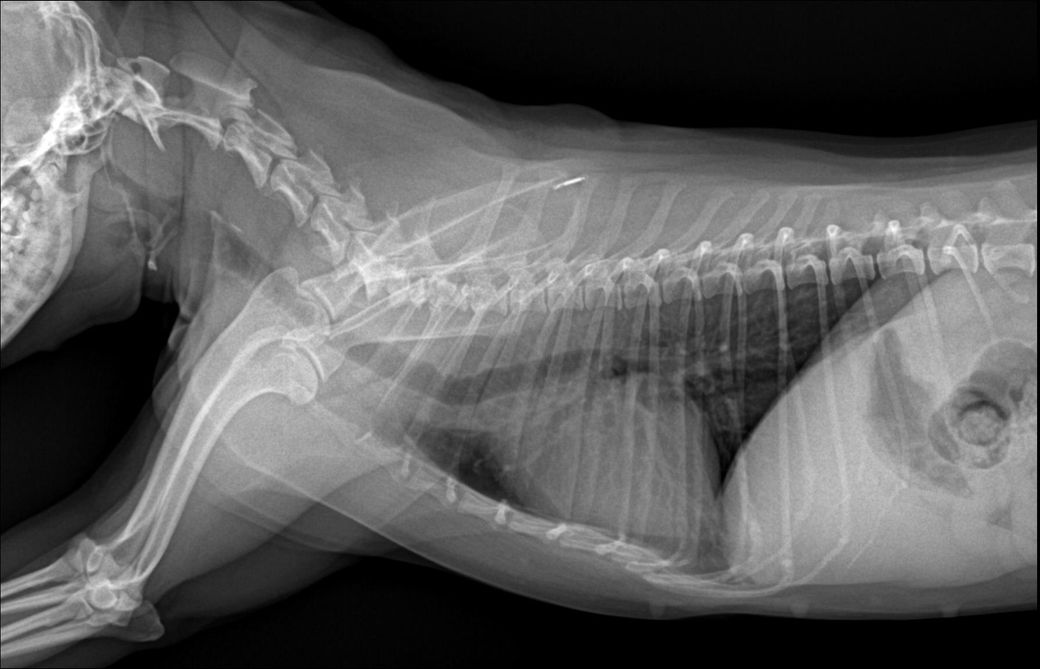

경추 4-5-6번의 추간판 사이가 좁아보이며 동시에 복부 방사선 촬영 시 결장에 가스가 많이 차 있는 것을 볼 수 있습니다.

복통이나 설사가 있을 수도 있겠네요